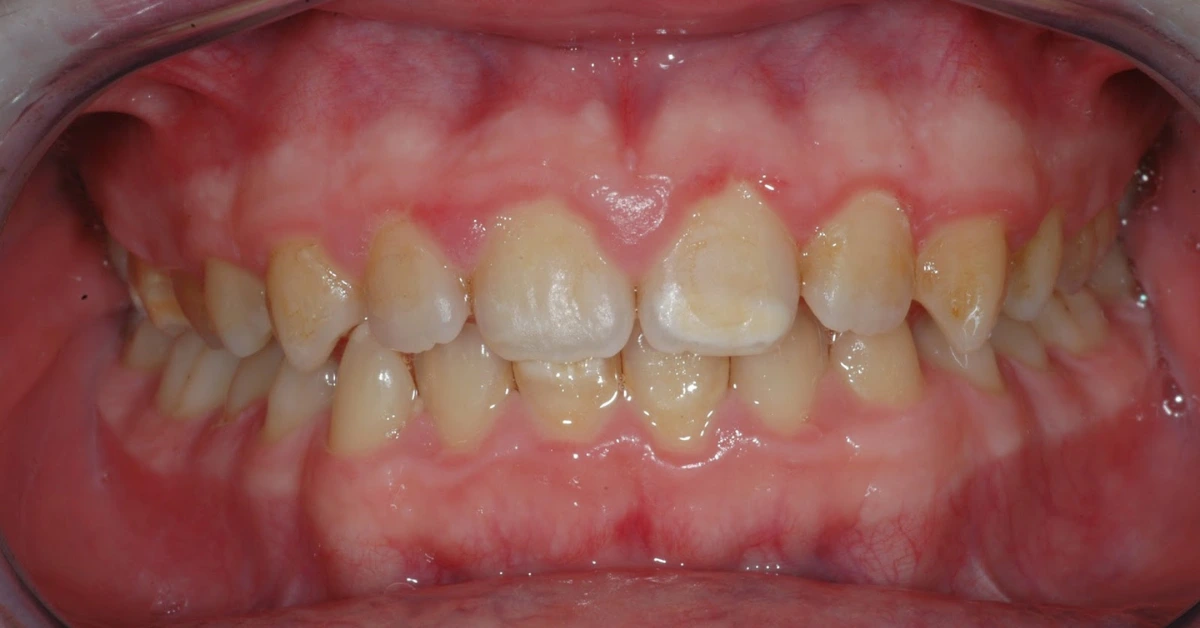

A sua origem resulta durante a amelogénese, numa disfunção dos ameloblastos em maturar o esmalte. Clinicamente verificam-se manchas (opacidades) na superfície dentária, que podem ter coloração branca leitosa, creme, amarela ou acastanhada, principalmente na região dos 2/3 mais incisais ou dos 2/3 mais oclusais. Quanto mais escuros forem os defeitos, mais fraco é o esmalte.

O principal problema desta condição é, nos molares, a elevada sensibilidade (pela porosidade) e susceptibilidade à fratura, e nos incisivos, é a estética.

O risco de cárie é bastante aumentado, dado terem pouco conteúdo mineral, sendo que as bactérias atingem facilmente as zonas de fratura. Para piorar, como a sensibilidade é grande, o simples estímulo mecânico da escovagem provoca dor, pelo que as crianças deixam de escovar com tanta regularidade.

Uma particularidade deste problema é que, quantos mais molares estiverem afetados, maior é a probabilidade de haver também defeitos nos incisivos e mais graves serão esses defeitos.